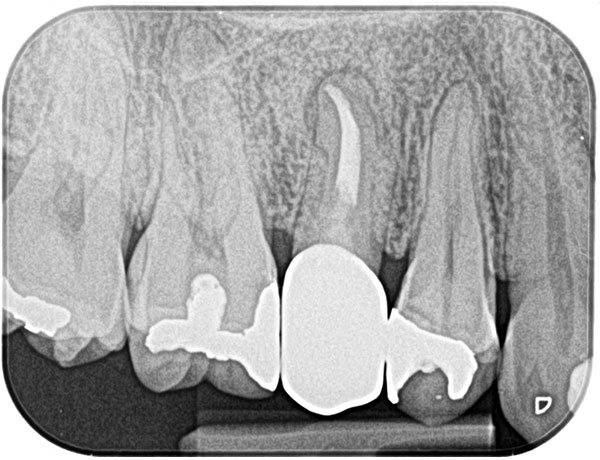

主訴: 右下がしみて痛い。

右下7根の根幹治療と親知らずの抜歯